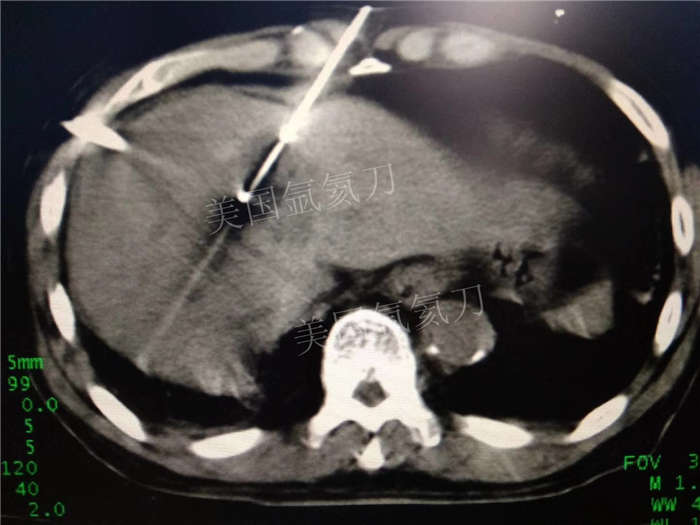

博罗人民医院乙状结肠癌术后肝转移化疗后冷冻消融